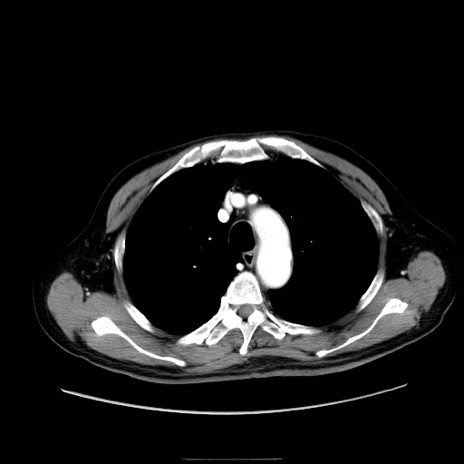

冠状断像

【症例】80歳代男性

【主訴】臍周囲痛

【現病歴】約6時間前から臍下部痛が出現。次第に腹部膨隆・背部痛も生じてきたため来院。背部痛の場所は変化しない。

【身体所見】意識清明、BT 36.3℃、BP  131/87mmHg、P 87bpm、SpO2 100%(RA)、臍周囲自発痛・圧痛あり、反跳痛なし、自発痛部位に一致して板状硬あり、腹部膨隆、腸雑音減弱、CVA tenderness両側陰性。

【データ】WBC 19600、CRP 0.33